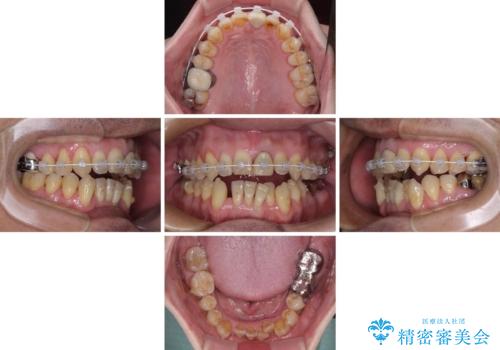

外科手術を併用した矯正治療を検討するほどに隙間の空いた開咬と、顕著な叢生が認められました。

開咬の改善には、舌の突出癖改善のためにトレーニングを行いつつ、インビザラインでの矯正治療が大変有効ですが、上顎骨が下顎骨に対して前方位に位置しており、インビザライン単独で治療を行うよりは補助装置とワイヤー矯正で奥歯の咬み合わせを改善してから、開咬改善のためのインビザライン矯正治療を行うこととしました。